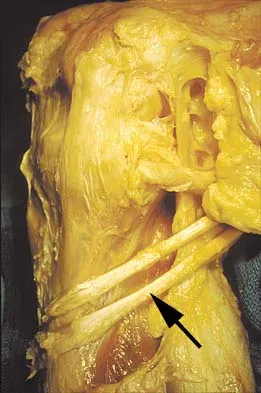

What muscle attaches to the site shown by the arrow in Figure 2?

Figure 11 shows the anatomic dissection of the medial side of the knee joint after removal of the superficial fascia. The arrow is pointing to what structure?